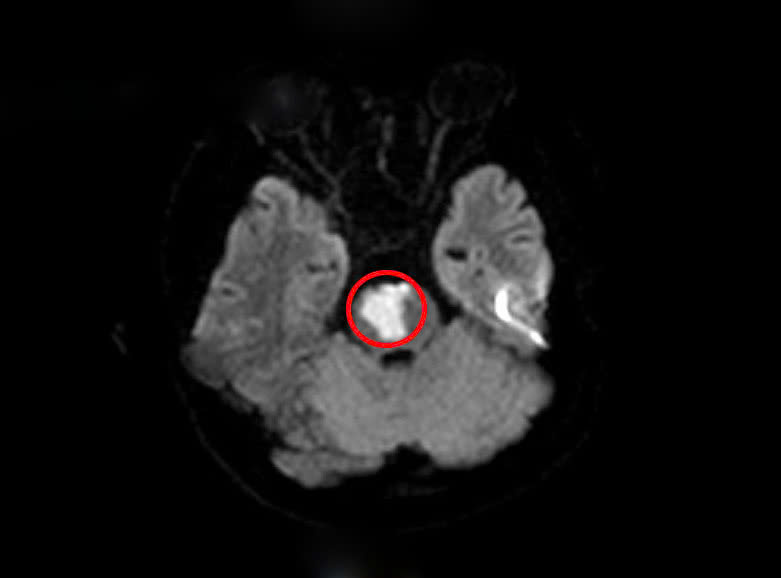

Sau khi khai thác tiền sử, các bác sĩ nghĩ nhiều đến tình trạng đột quỵ não và cho chỉ định tiến hành chụp MRI sọ não. Kết quả cho thấy người bệnh có khối nhồi máu tiểu não, cầu não do tắc động mạch thân nền.

Tổn thương nhồi máu vùng tiểu não của người bệnh(Vùng khoanh tròn màu đỏ)

Theo bác sĩ, trên kết quả xét nghiệm máu có rối loạn lipid máu, một yếu tố nguy cơ dẫn đến các vấn đề tim mạch và mạch máu não. Ngoài ra khi làm các xét nghiệm chuyên sâu, người bệnh được phát hiện bất thường trong hệ gen gây tăng nguy cơ tạo huyết khối tắc mạch.